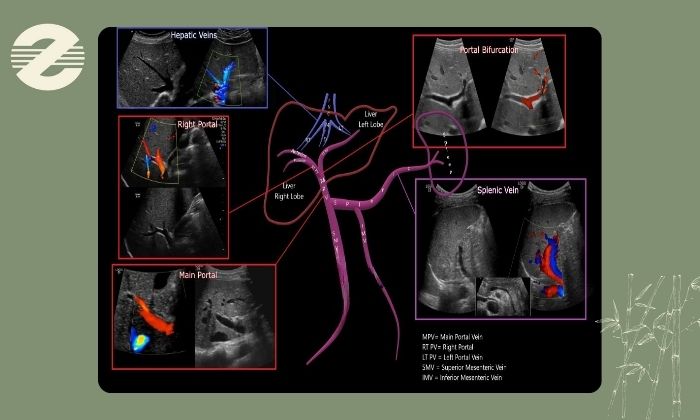

سونوگرافی کالر داپلر پورت (Color Doppler of Portal Vein) یک روش تصویربرداری تخصصی برای بررسی سیستم ورید پورتال است؛ سیستمی که خون را از دستگاه گوارش، طحال و پانکراس به سمت کبد انتقال می‌دهد. این تکنیک با استفاده از امواج صوتی جریان خون داخل ورید پورتال را نشان می‌دهد و به پزشک کمک می‌کند سرعت، جهت و کیفیت جریان خون را ارزیابی کند.

در این روش علاوه بر تصویر سیاه‌ و سفید سونوگرافی، رنگ‌های متفاوت جریان خون را نمایش می‌دهند؛ معمولاً رنگ قرمز و آبی بر اساس جهت حرکت خون نسبت به پروب استفاده می‌شود. این ویژگی باعث می‌شود اختلالاتی مثل تنگی، انسداد، لخته (ترومبوز)، فشار پورت بالا، وریدهای فرعی غیرطبیعی یا تغییرات ناشی از بیماری‌های کبدی راحت‌تر و دقیق‌تر تشخیص داده شوند.

پس از قرار دادن ژل مخصوص روی پوست سمت راست شکم پروب سونوگرافی حرکت داده می‌شود و با استفاده از داپلر رنگی و طیفی، جریان خون عروق کبدی از جمله ورید پورت، وریدهای کبدی و شریان کبدی بررسی می‌گردد.